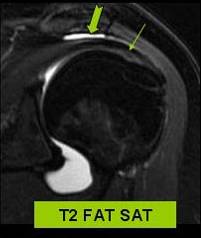

RUPTURA PARTIALA PROFUNDA A SUPRAEPIFIZARULUI

STG. LONGITUDINSIAL - TRANSVERSAL

DR STG

UMAR DUREROS CRONIC

Fisura partiala a fetei articulare a versantului anterior al supra epifizarului

Confirmare IRM